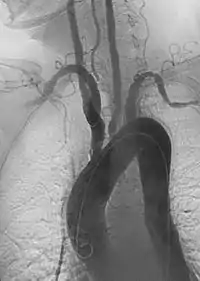

Цей синдром відносять до системних васкулітів. Приблизно у половини пацієнтів з'являються первинні соматичні симптоми: стомлюваність, гарячка, розлади сну, втрата ваги, біль у суглобах. Доволі часто синдром перебігає з анемією, лейкоцитозом, підвищенням рівню С-реактивного білку та збільшенням швидкості осідання еритроцитів. Пізніше гострофазові реакції згасають, але зберігається підвищений рівень імуноглобулінів, показники бластної трансформації лімфоцитів. Ця стадія поступово завершується і переходить у хронічну, що характеризується запаленням аорти та її відгалужень. У інших хворих на синдром Такаясу з'являються лише пізні зміни кровоносної системи без попередніх ранніх соматичних симптомів. На пізніх стадіях слабкість стінок артерій може привести до виникнення локалізованих аневризм. Також цей синдром може спричинити хворобу Рейно.